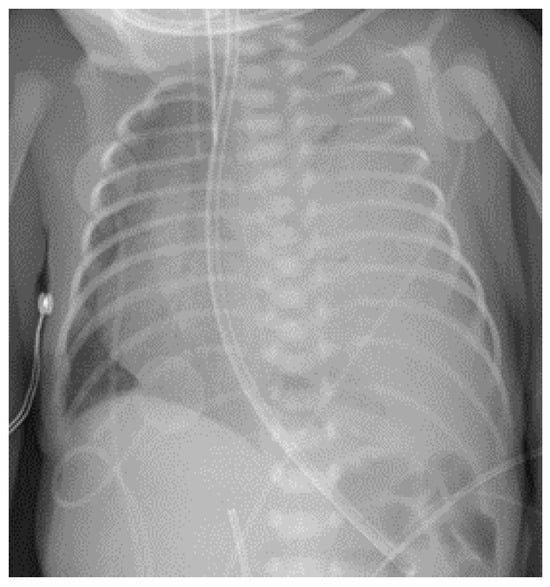

2. Case Presentation